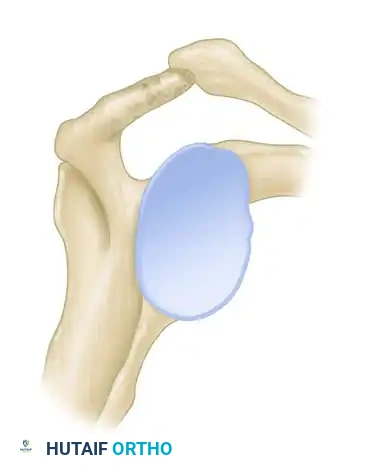

Figure 46-4 (Type III): A hooked acromion with a prominent anterior-inferior projection. This morphology severely compromises the supraspinatus outlet.

Cadaveric studies have demonstrated a profound correlation between acromial morphology and rotator cuff integrity. In a landmark study of 140 shoulders, 73% of all full-thickness rotator cuff tears were found in shoulders possessing a Type III (hooked) acromion. Patients with a decreased acromial slope are inherently predisposed to subacromial stenosis and subsequent mechanical attrition of the underlying tendons.